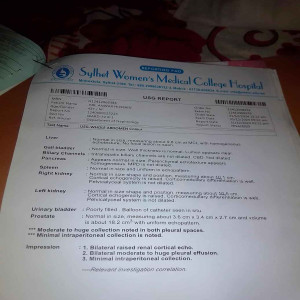

#250909I: জটিল কিডনি সমস্যায় আক্রান্ত শহিদুল ইসলাম চিকিৎসার জন্য সাহায্য চেয়েছেন, গ্রাম: মহব্বতপুর, জেলা: দিনাজপুর।